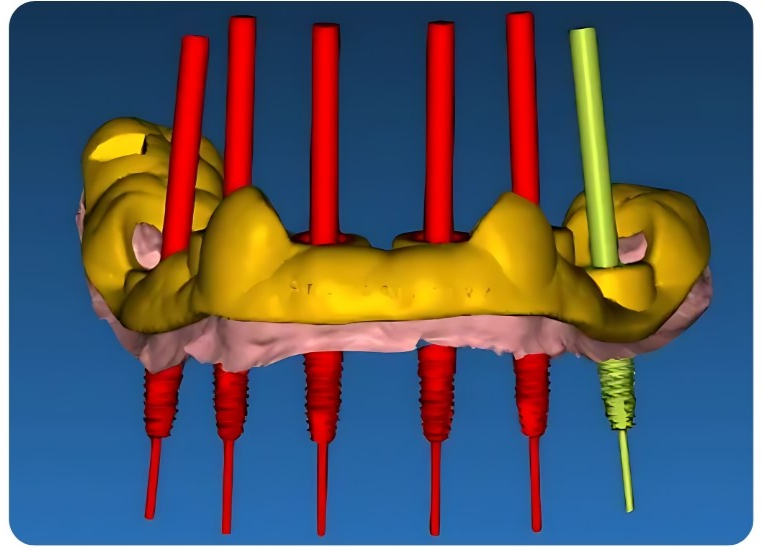

💻 2.PLANIFICACIÓN VIRTUAL

Comunicación por llamada o chat con nuestros odontólogos para finalizar la planificación.